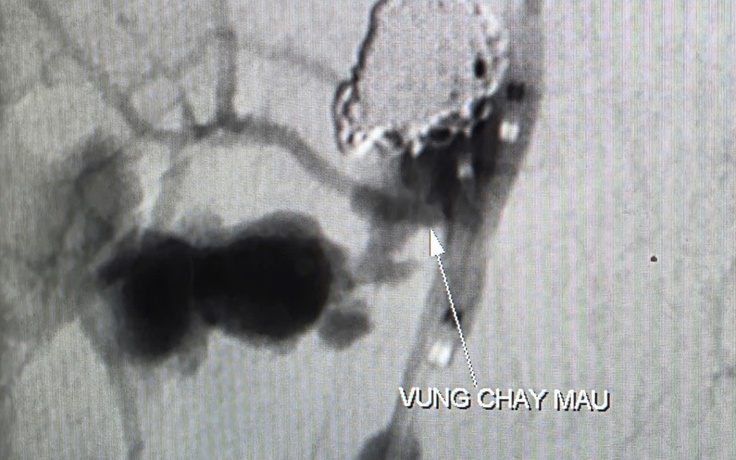

Cứu sống bệnh nhân ung thư chảy máu ồ ạt

Nữ bệnh nhân bị ung thư vòm hầu, đang hóa trị, được chuyển đến bệnh viện trong tình trạng chảy máu nhiều từ mũi và miệng, kèm khó thở, huyết áp thấp nguy kịch.